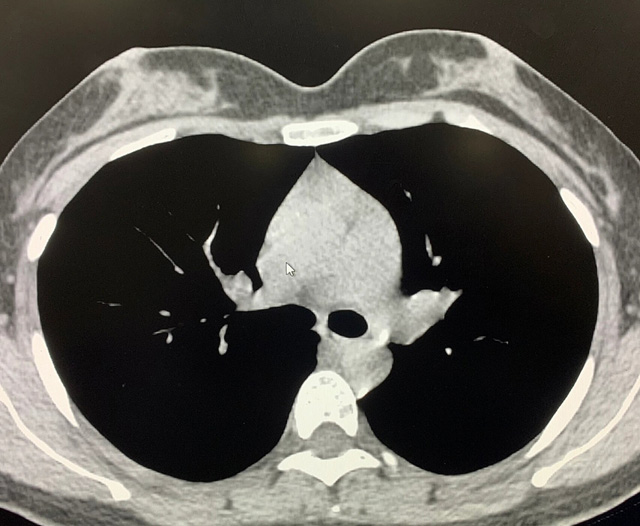

能譜純化技術(shù)的核心是通過物理濾過(如錫濾片)或軟件算法,選擇性濾除低能X射線光子,保留高能光子。在胸部低劑量CT掃描中顯著提升了圖像質(zhì)量與輻射劑量的平衡。

優(yōu)勢輻射劑量顯著降低相較于常規(guī)CT,輻射劑量減少約70%-90%,尤其適合需多次隨訪的高危人群(如肺癌篩查),降低輻射相關(guān)癌癥風(fēng)險早期肺癌篩查效果明確可清晰檢測毫米級肺結(jié)節(jié),顯著提高早期肺癌檢出率,降低死亡率。檢查快捷且普及性高單次掃描僅需數(shù)秒,無需對比劑,設(shè)備廣泛配置于基層醫(yī)院,便于大規(guī)模篩查。長期成本效益顯著雖單次費用與常規(guī)CT相近,但早期干預(yù)可大幅降低晚期治療費用及社會醫(yī)療負擔(dān)。技術(shù)優(yōu)化提升圖像質(zhì)量迭代重建算法(如ASIR、MBIR)在降低劑量同時減少噪聲,平衡影像質(zhì)量與安全性。